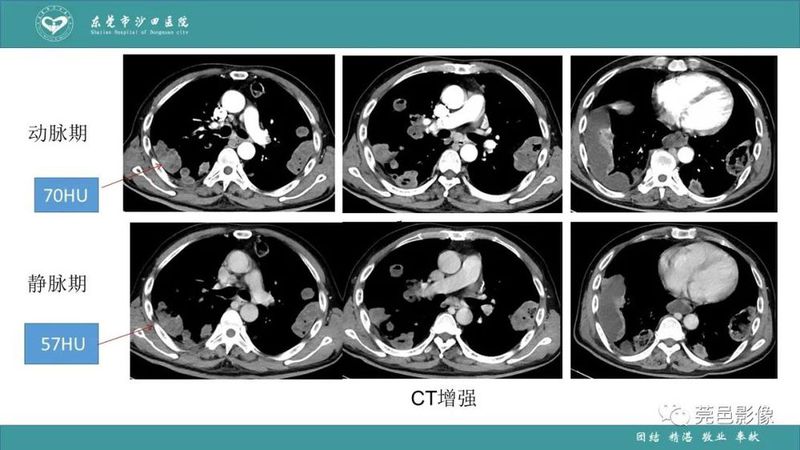

「肺炎克雷伯杆菌肺炎」影像学诊断+鉴别诊断